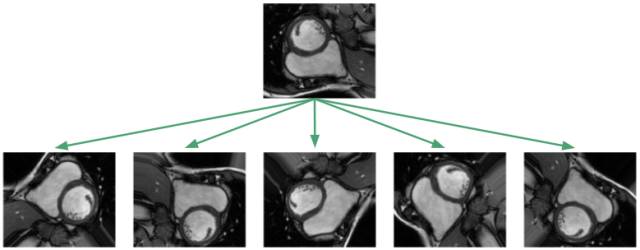

由于数据集过小,人们可能会怀疑无法将其一般化到尚未看到的图像!但是很不幸,医疗上标记过的数据非常昂贵,并且很难获取到。对数据集进行处理的标准程序是对图像应用仿射变换:随机旋转、平移、缩放和剪切。此外,我实现了弹性变形,也就是对图像的局部区域进行拉伸和压缩。

应用这种图像增强算法的目的是为了防止神经网络只记住训练的样例,并强迫其学习RV是一个实心的、月牙形的、方向任意的物体。在我实现的训练框架中,我会随时对数据集应用图像变换算法,这样,神经网络就会在每次训练时看到新的随机变换。